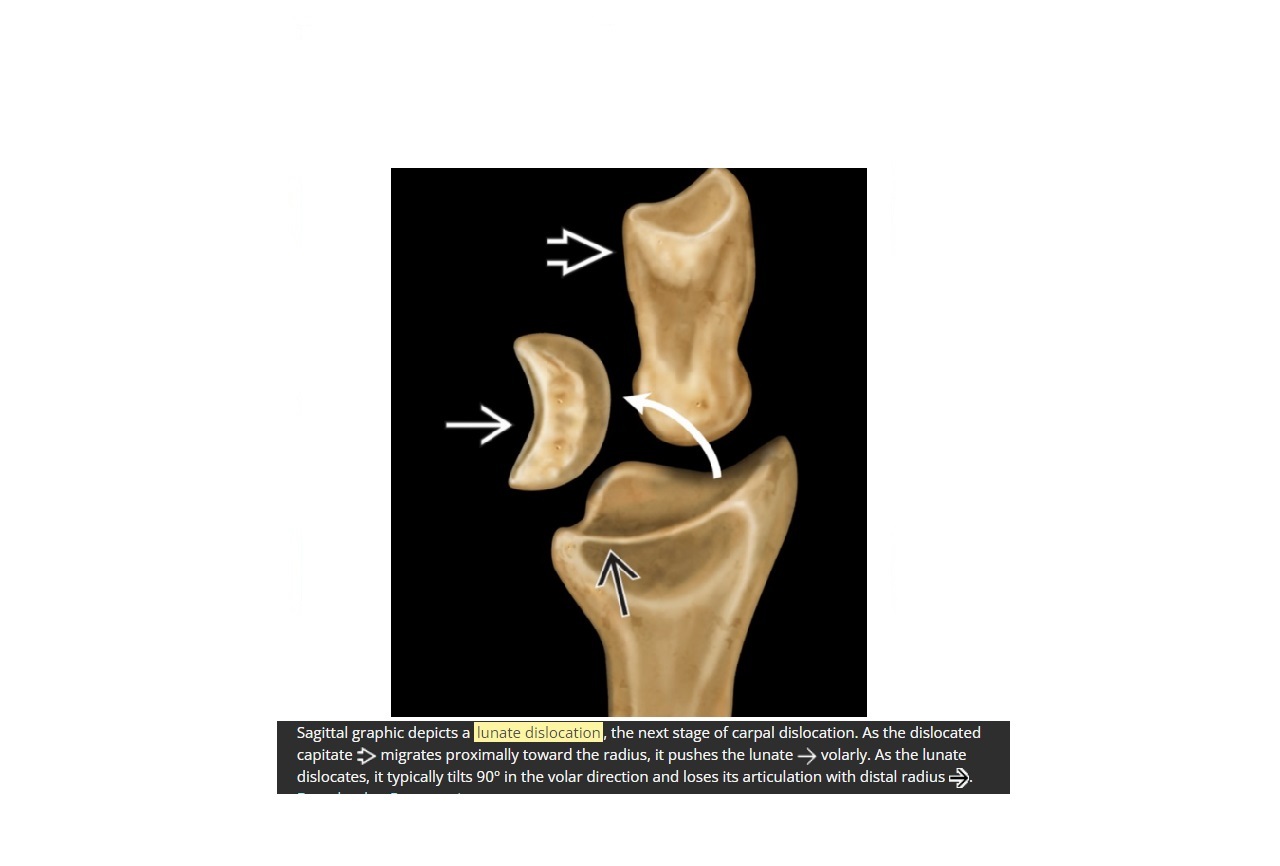

Lunate dislocated volar direction

Ligament damaged = Dorsal radio lunate ligament